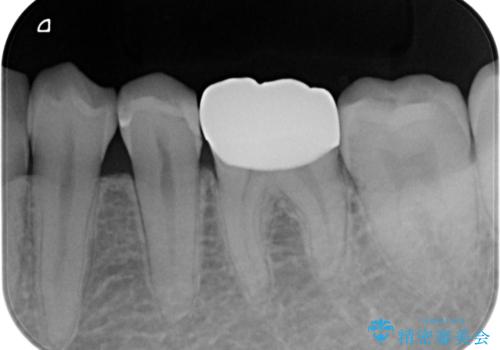

精度の低い詰め物のやり替え

- セラミックのつめものの精度が低かったためやり直しを行いました。

歯の高さがなく、またセラミックアンレーは割れるリスクが高いため、セラミックのアンレーとはせず、クラウンとし、さらに割れにくいようにヴェレッツァクラウンとしました。

- 合計 17.6万円(内訳 左下7:e-max インレー 7.7万円、左下6:セラミッククラウン(ヴェレッツア 8.8万円)、仮歯 1.1万円)費用は治療当時の料金となります